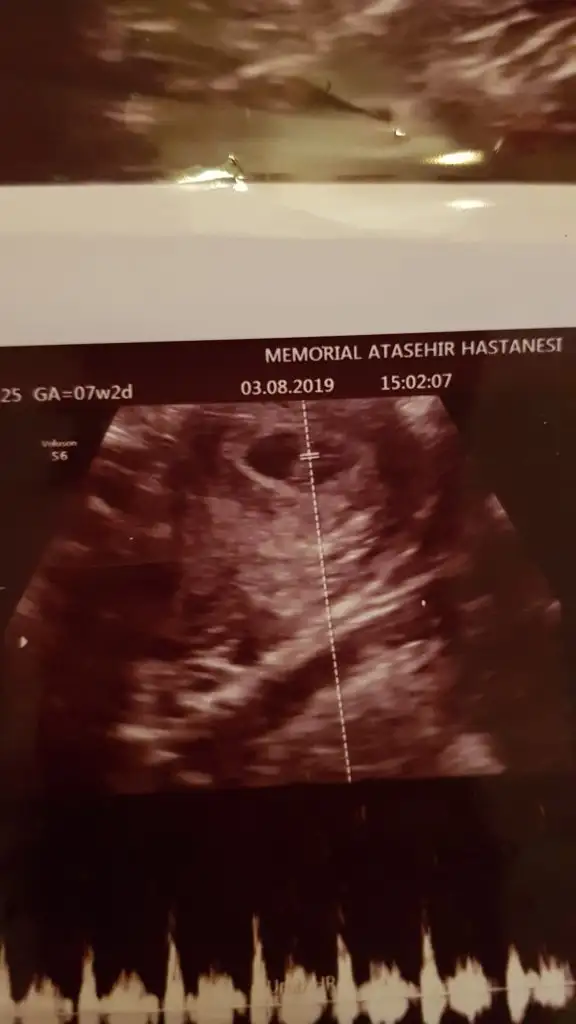

Buna göre kız ama 6 yada 7 hafta usg olmalıBana da bir yorum yapabilir mısınız arkadaşlar ? 8 hafta 1 günlük

Bebeğinizin kalp atışını 7+2 de mi duymuştunuz ilk defa?

EvetBebeğinizin kalp atışını 7+2 de mi duymuştunuz ilk defa?